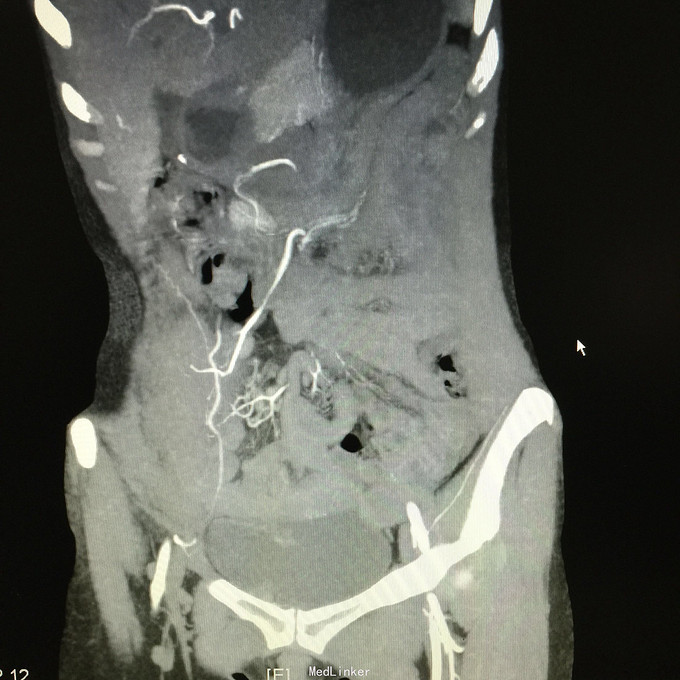

查体无特殊。 辅助检查:中下腹CT平扫+增强+CTU+CTA示:1.右输尿管中上段病变,考虑恶性病变,周围多发淋巴结转移,髂总动脉及髂外动脉起始部、髂内动脉中上段受侵闭塞,右侧腰大肌可疑受侵;建议输尿管镜检查;右肾重度积水,右肾功能明显受损。2.CTA示:右肾动脉纤细,肝右动脉起源于肠系膜上动脉。3.子宫体密度不均匀,建议MRI检查。中下腹MRI平扫+增强+MRU检查结果类似。

患者术后2月出现反复臀部疼痛,左侧为主,疼痛跑迷宫为隐痛,于翻身及活动时加重,卧床休息可稍缓解,多于下午出现,伴有发热,最高达39℃,在当地医院予“氟康唑”及止痛治疗后稍有缓解,但仍反复发热。后疼痛加剧,并出现双下肢疼痛,以大腿外侧为主,无间歇性跛行,无小腿及双足麻木疼痛不适,行对症治疗后效果不佳,于2015-10-9再次返院,予消炎止痛、营养支持及营养神经等治疗。查CT及MRI均提示骶髂关节炎症及腹膜后巨大病变,右侧髂总动脉及髂内、外动脉上段、右侧腰大肌受累。2015-10-15 14:00患者出现右下肢剧烈疼痛、右下肢乏力和麻木,随后出现2次血便,每次量约100ml,暗红色,无腹胀、腹痛等不适,查血提示白细胞 28.17*10E9/L,中性粒绝对值 25.33*10E9/L,血红蛋白56g/L,予止血、输血、抗真菌、止痛等治疗。19:00再次出现右下肢剧烈疼痛伴右下腹痛,查体:BP 80-90/50-60mmHg,P 100-106次/分,R 23次/分,SpO2 100%。右下腹轻压痛,反跳痛阴性,右下肢蹲背伸及踝背伸肌力II-III级,立即行全腹CT检查,示右髂总动脉假性动脉瘤破裂,予加强输注浓缩红细胞及补液支持治疗。清介入科会诊,考虑脓肿和感染为介入血管腔内支架置入治疗的禁忌症,建议予血管外科行开放手术,予患者及家属沟通,并转外院血管外科进一步治疗。